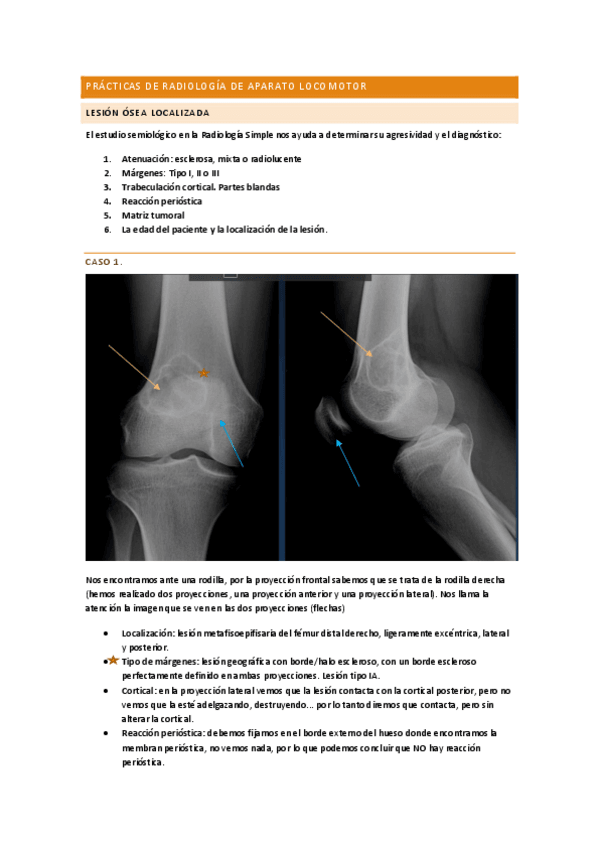

Prácticas de Radiología

He publicado nuevos apuntes de 2º Radiologia General: Prácticas de Radiología

Practica-musculoesqueletico.pdf